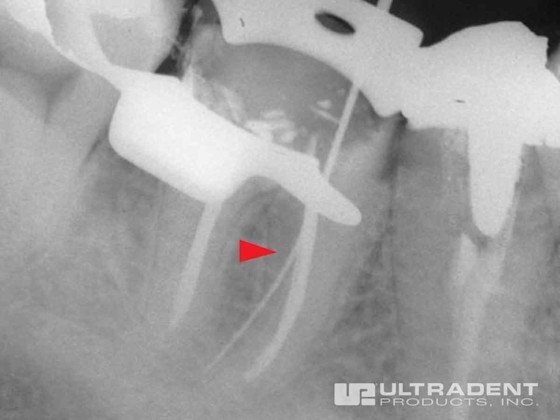

Effective Perforation Repair

Perforation located in the cervical third of the mesial buccal canal.

MTA cement in place showing repair.